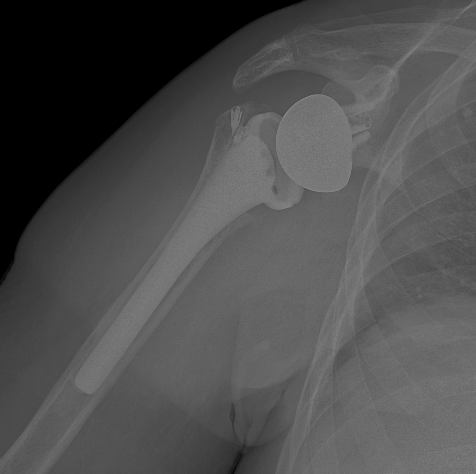

Ejemplo radiográfico

Radiografía simple mostrando prótesis de hombro

Placa simple que muestra prótesis de hombro y su relación con artefactos